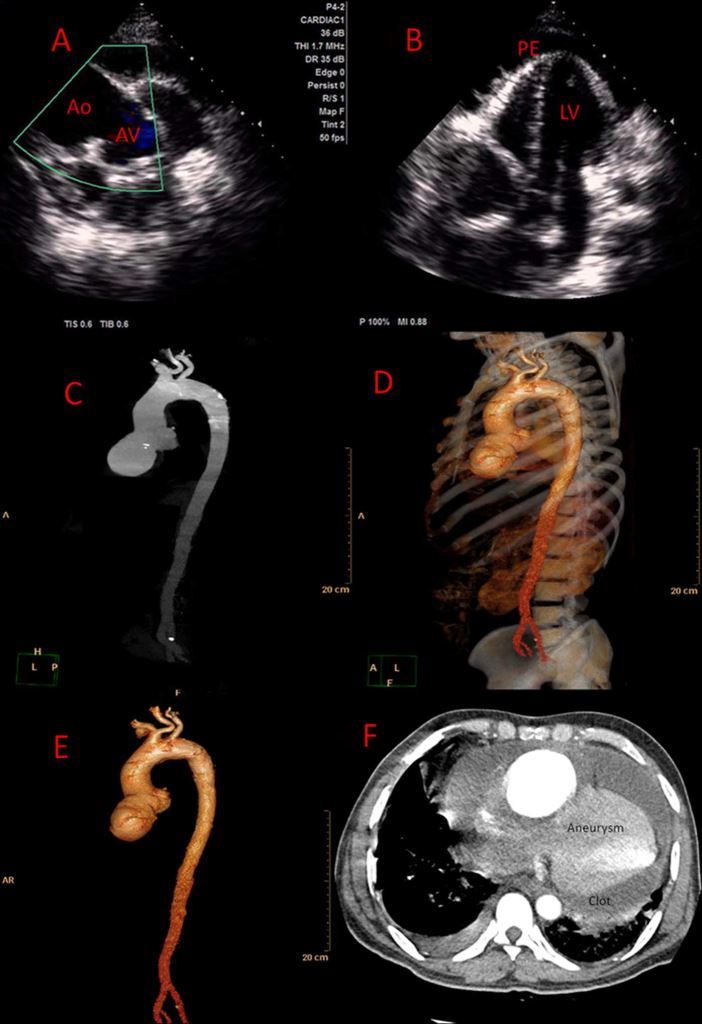

test. 2D echocardiography demonstrated moderate pericardial

effusion, normal biventricular function with dilated and

aneurysmal ascending aorta and mild aortic regurgitation

(figure 1A,B). Pleural fluid aspiration showed straw coloured

The patient was started on antitubercular therapy. CT

aortogram confirmed the presence of a giant (7.1×8.5 cm)

aneurysm of the right sinus of valsalva (figure 1C–F). The